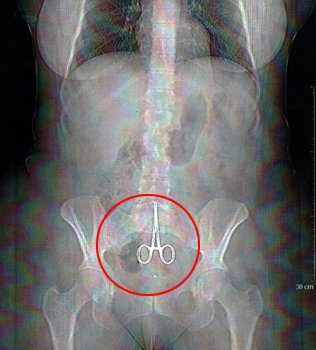

Hai trường hợp trên, các bác sĩ đã để quên kéo trong bụng của bệnh nhân sau khi phẫu thuật. Trường hợp thứ hai, trong cơ thể bệnh nhân có tới 2 cái kéo.